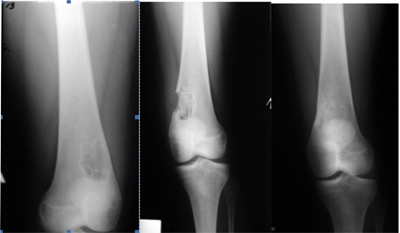

| Рисунок 1. Больная Р. 12 лет. Солитарная киста верхней трети левой плечевой кости: | ||

| а) рентгенологическая картина состояния до операции; | б) через 4 месяца после пластики дефекта пластинами ДКИ «Перфоост»; | в) через 11 месяцев после проведенной операции. |